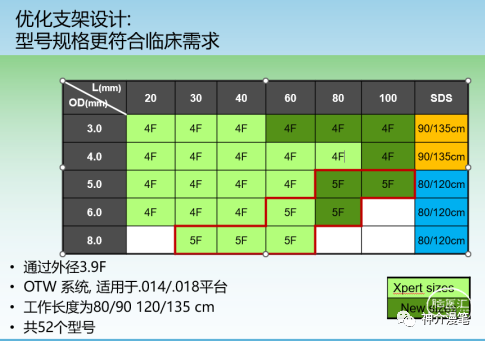

说一下雅培的Xpert支架吧,整体来说是个挺有想法的支架。号称复合设计,其实归根还是个开环支架,最大的特点是壁薄,外径小,可以经过更小的导管和鞘输送,对于迂曲通路这是一个好的设计。

3-6的支架可以使用4F鞘或6Fguiding进行释放,下图为其常见支架型号。